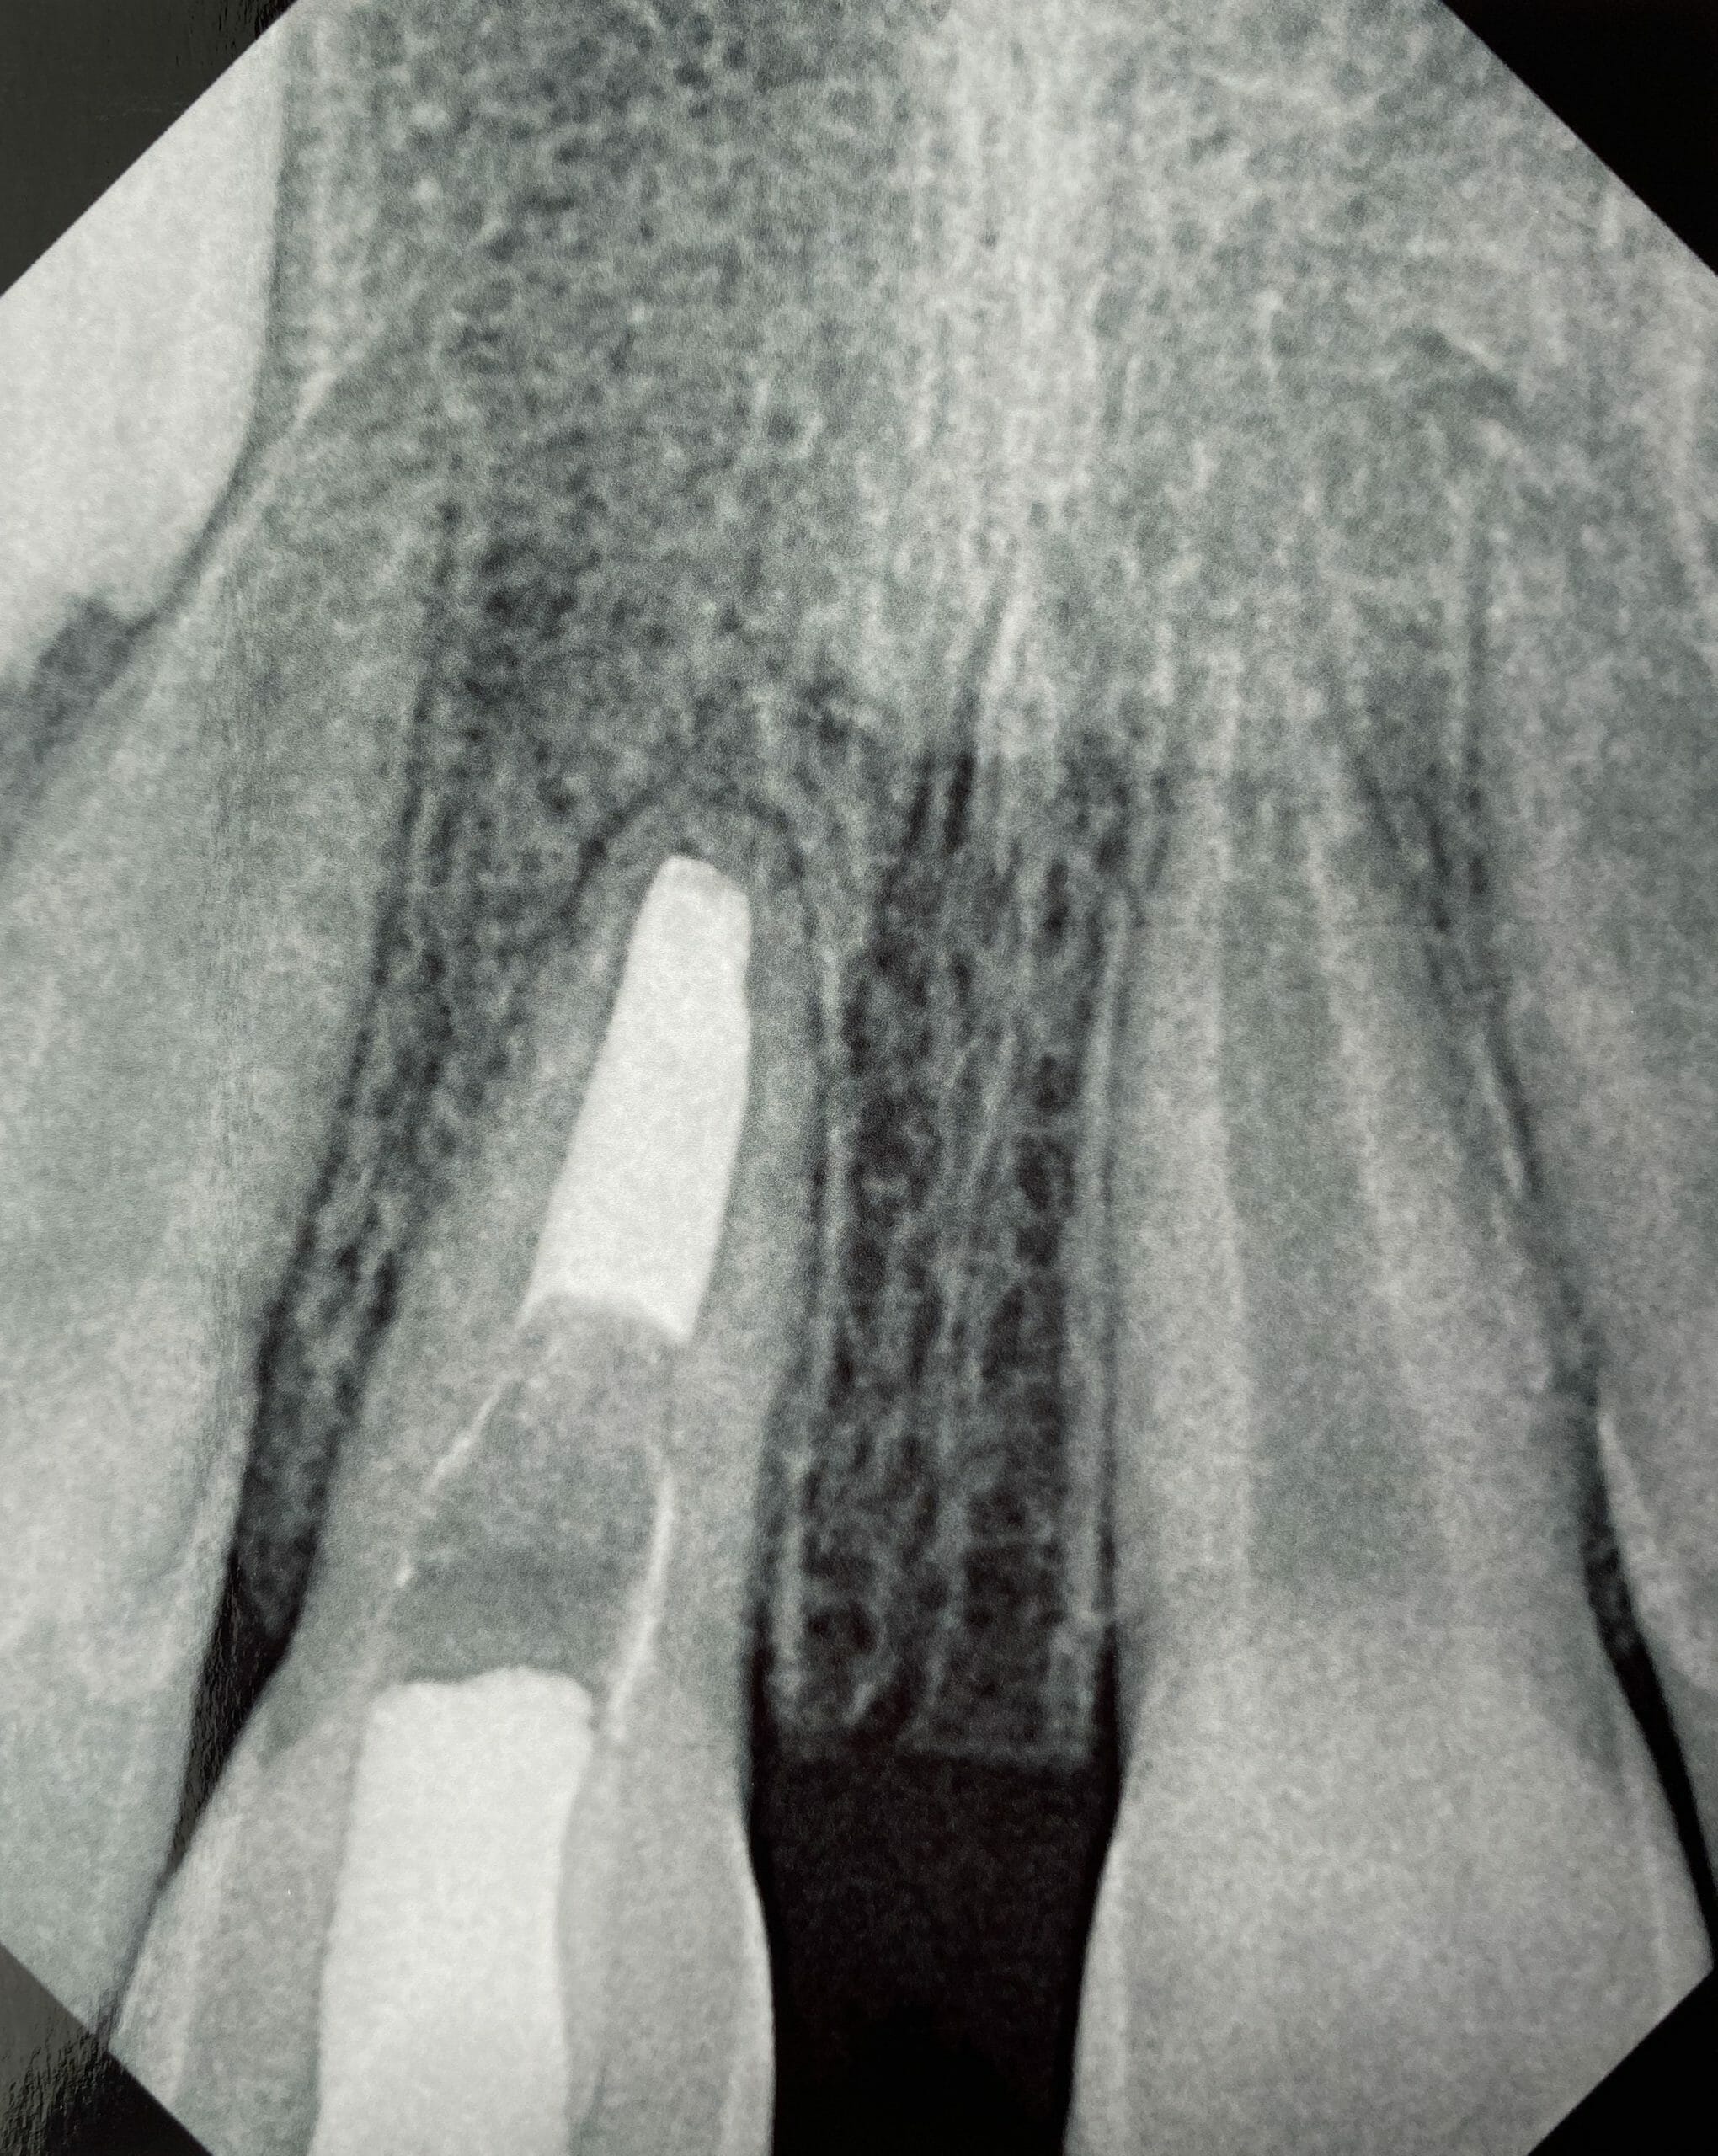

Apexification with Ca(OH)2

Click on an x-ray image below to see a larger version: